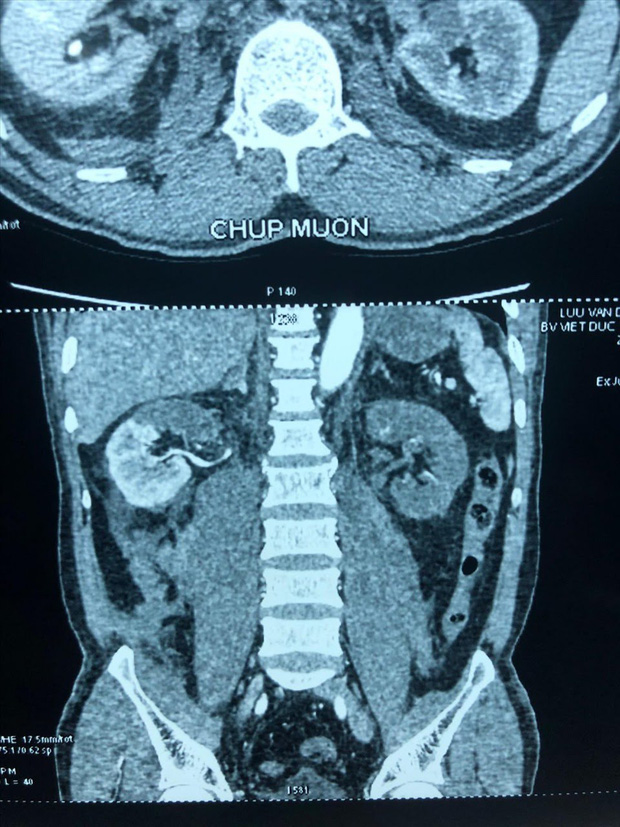

Tai nạn giao thông khiến anh L.V.D. (57 tuổi, Kim Thành, Hải Dương) bị tổn thương tắc động mạch thận. Bệnh viện Hữu nghị Việt Đức phát hiện thận bên phải của bệnh nhân có huyết khối động mạch cực trên, mất phần cấp máu cho cực trên, thận bên trái thiếu máu hoàn toàn, chức năng thận giảm, có biểu hiện suy thận.

Sau hội chẩn liên khoa, các bác sĩ chuyên khoa Tiết niệu - Tim mạch - Ghép tạng đã quyết định mổ cấp cứu, cố gắng bảo tồn thận phải và cứu thận trái cho bệnh nhân.

TS Lê Nguyên Vũ, Trung tâm Ghép tạng – Bệnh viện Hữu nghị Việt Đức, người trực tiếp tham gia ca phẫu thuật cho biết, thông thường với những tổn thương tắc động mạch thận, phẫu thuật sớm từ giờ thứ 6-8 tiếng sau tai nạn mới có thể cứu được thận. Tuy nhiên, bệnh nhân này khi được chuyển vào phòng mổ đã bước sang giờ thứ 24, quá "thời gian vàng" cho một ca ghép thận tự thân.

Nếu bệnh nhân không có biểu hiện suy thận thì không cần ghép thận tự thân và sống bằng thận còn lại. Nhưng anh D. đã có dấu hiệu suy thận nên các bác sĩ bắt buộc phải tiến hành ghép thận tự thân để 2 thận vẫn bổ sung chức năng cho nhau.

Nhóm phẫu thuật chia làm 2 kíp, tiến hành song song rửa – ghép thận trái và kiểm tra các tạng trong bụng, cơ hoành và bảo tồn thận phải.

Thận trái sau khi lấy ra khỏi cơ thể đã được rửa bằng dung dịch, bơm dung dịch tiêu huyết khối để hy vọng đẩy máu cục trong các mạch máu nhỏ bên trong quả thận. Mất khoảng 30 phút sau khi rửa, thận có màu trắng và đã được ghép vào hố chậu trái.

Sau 10 ngày phẫu thuật, chức năng thận của người bệnh đã trở lại bình thường.

PGS.TS Đỗ Trường Thành – Trưởng khoa Phẫu thuật Tiết niệu cho hay, "Thật sự là điều kỳ diệu! Quả thận của bệnh nhân mặc dù bị thiếu máu rất lâu nhưng các mạch máu trong thận không bị tắc lại, thận sau khi rửa không tím đen. Đây là một may mắn cho bệnh nhân có thể giữ lại được quả thận đảm bảo chức năng sống lâu dài".